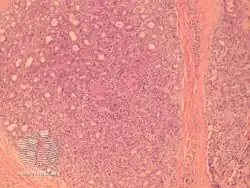

Aggressive digital papillary adenocarcinoma is a cutaneous condition characterized by an aggressive malignancy involving the digit between the nailbed and the distal interphalangeal joint spaces.[1]:โ670โ

Aggressive digital papillary adenocarcinoma-pathology